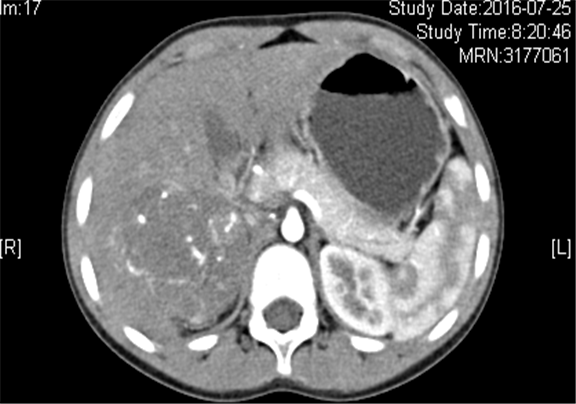

上腹部增强CT示:右侧肾上腺区占位性病变,考虑恶性肿瘤,右侧肾上腺神经母细胞瘤可能性大,请结合临床综合评价。

术前CT检查:

动脉期

静脉期

平衡期